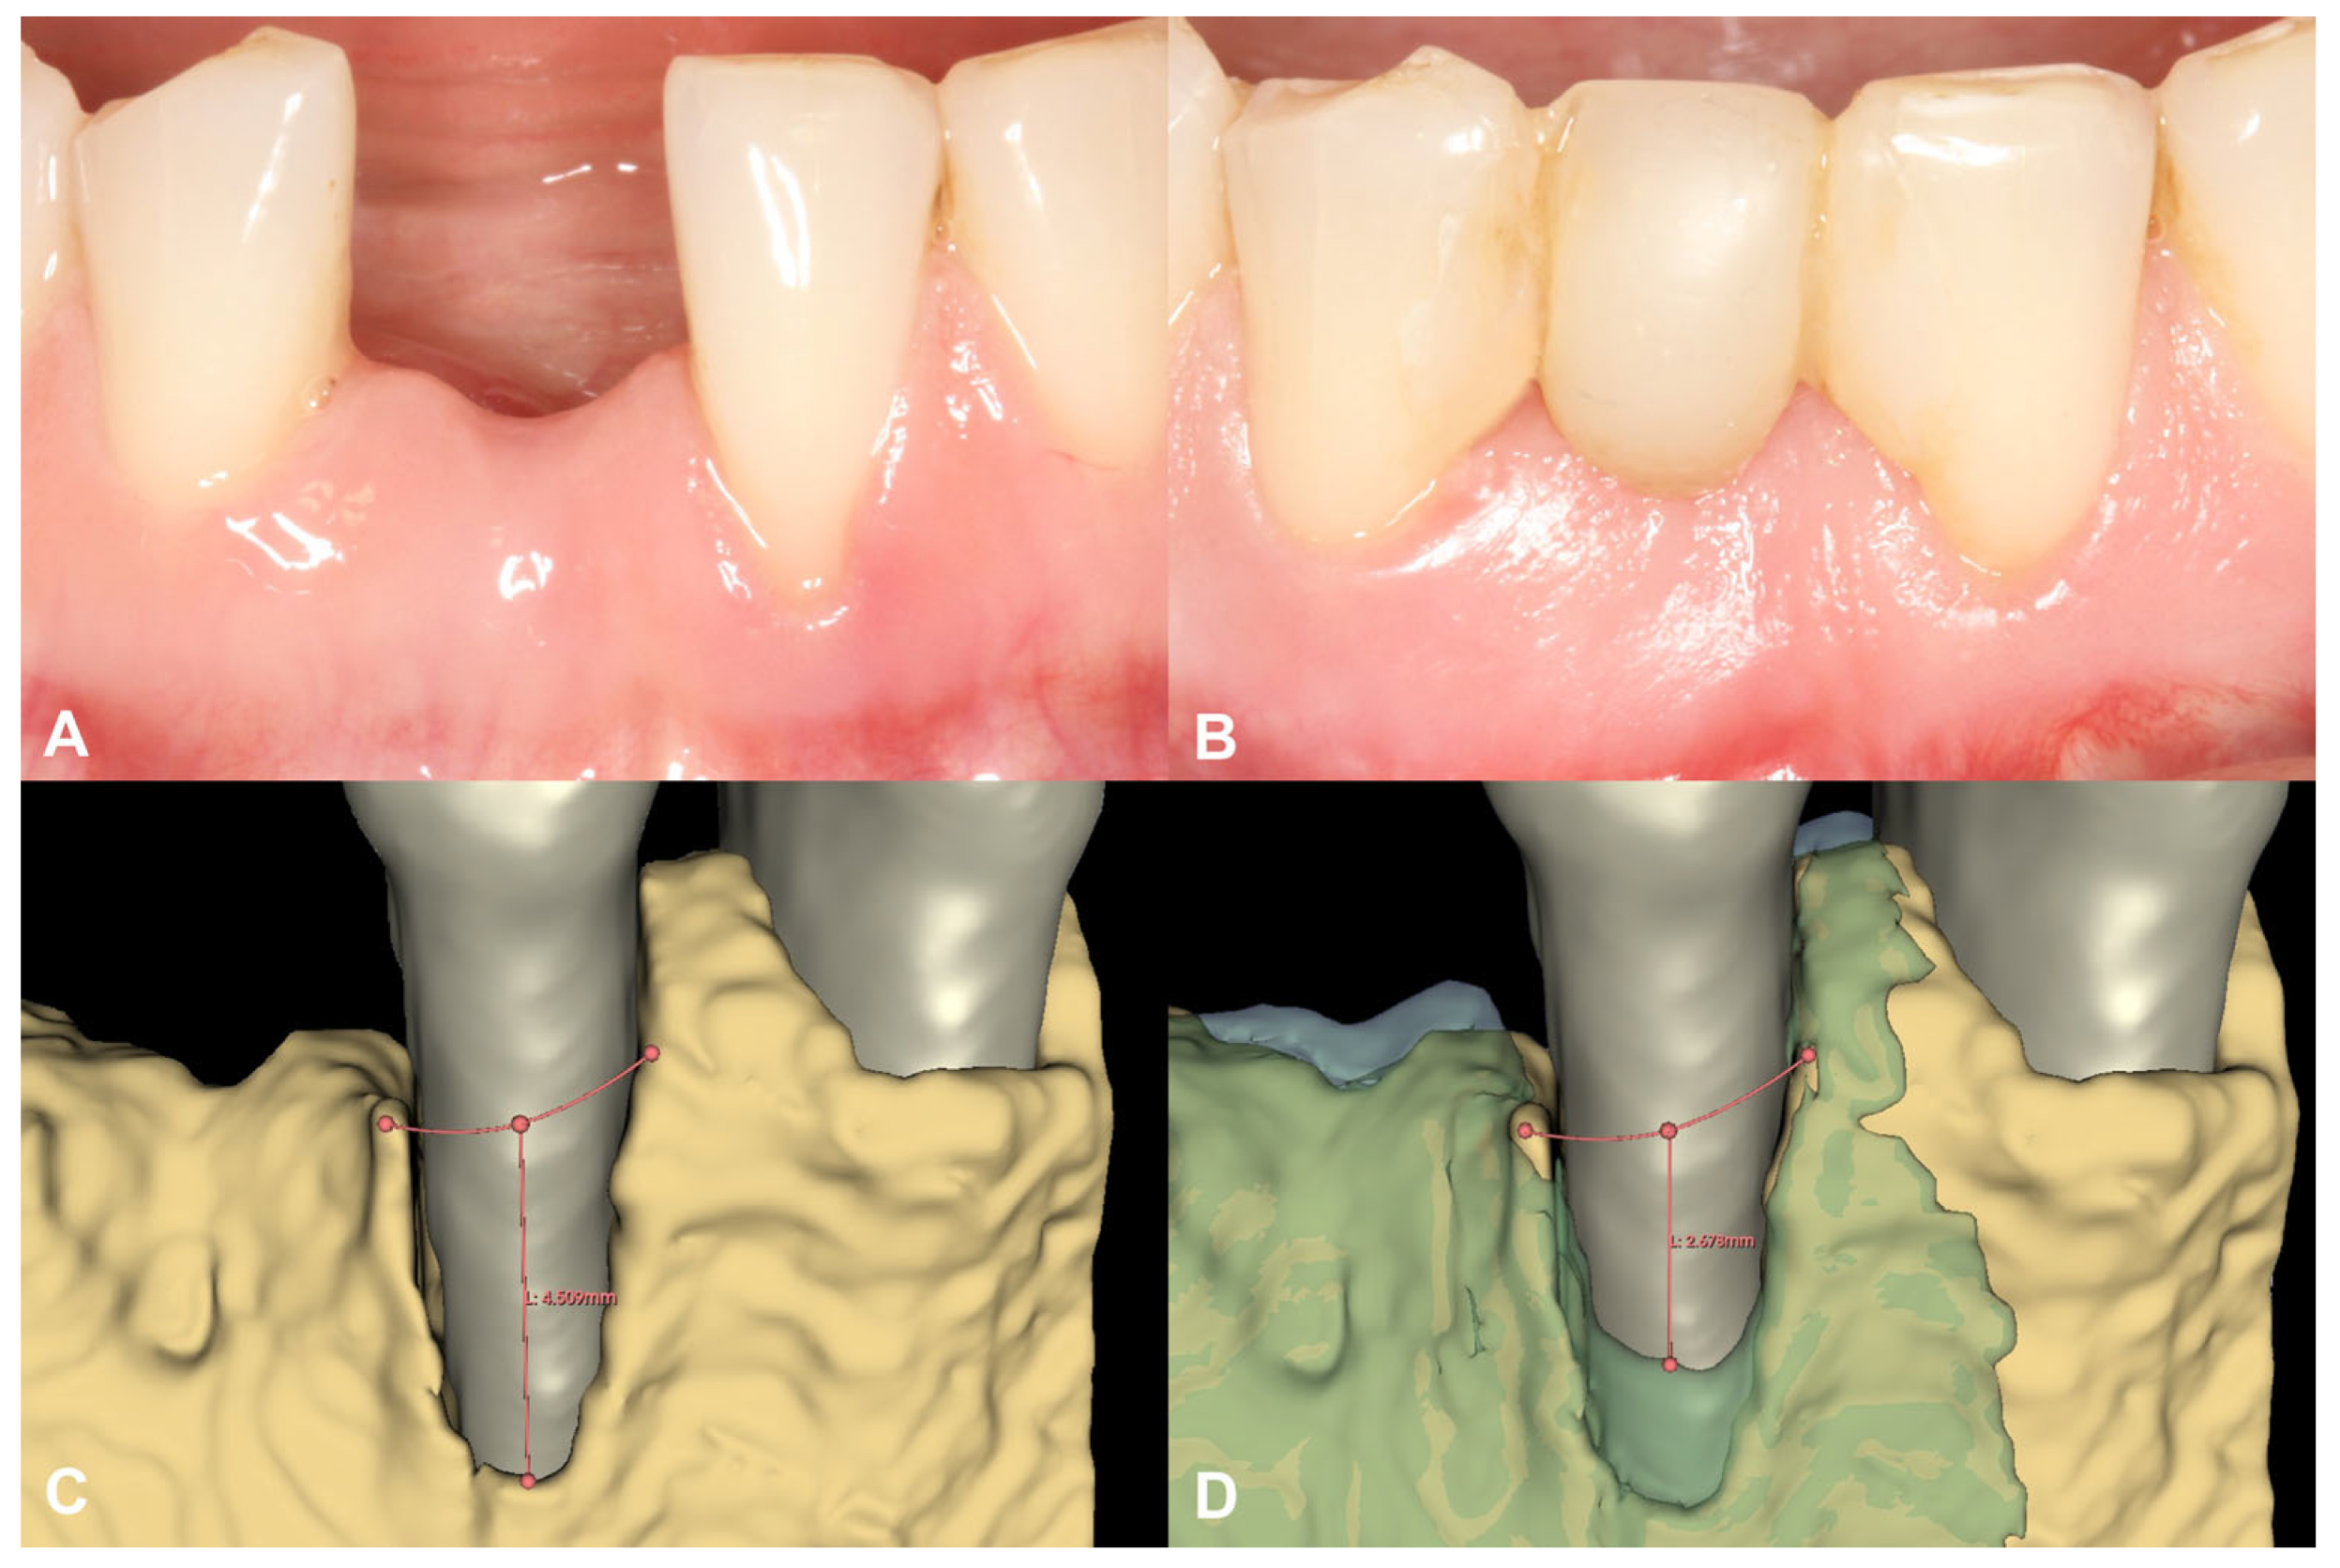

Figure 4.

Soft tissue conditions and radiographic hard tissue changes around Tooth 31 (Case #1). (A): Soft tissue conditions at baseline, Miller Class III recession at Tooth 31; (B): Soft tissue conditions at six-month follow-up, resolution of the recession at Tooth 31; (C): Baseline buccal alveolar bone dehiscence measured at 4.51 mm at Tooth 31; (D): Partial resolution of the buccal alveolar bone dehiscence at Tooth 31, residual depth: 2.68 mm.

3.1.2. Short-Term Hard Tissue Gain and Two-Year Follow-Up

Following spatial alignment and 3D subtraction, a volumetric hard tissue gain of 0.12 cm3 was detected (Figure 3A,B). At the deepest point of the defect, a 0.79 mm vertical hard tissue gain was measured, while horizontal hard tissue gains of 0.93 mm, 1.23 mm, and 1.38 mm were observed at 1, 2, and 3 mm-s apical to the top of the alveolar crest, respectively (Figure 3C,D). The initially measured dehiscence at Tooth 31 was reduced to 2.68 mm (Figure 4).

Similar to the study by Elad et al. [13], the first case in the current paper used the magnesium membrane as a wall on the buccal aspect in conjunction with a bilayer tunnel approach. By pre-bending the membrane, the ideal curvature of the alveolar ridge in the lower anterior region could be re-established. While collagen barrier membranes are generally difficult to manipulate when combined with a tunnel approach, the rigidity of the NovaMag® promotes this material as an ideal alternative. The hard tissue gain was observed at the edentulous crest and a partial resolution of the buccal bone dehiscence was evident at the adjacent tooth. This resulted in soft tissue coverage of the Miller Type III gingival recession.